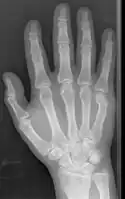

Boxer's fracture of the 5th metacarpal head from punching a wall

A boxer's fracture is the break of the metacarpal bone of the hand near the knuckle at the base of the little finger.[2] Occasionally it is used to refer to fractures of the 4th metacarpal as well.[1] Symptoms include pain and a depressed knuckle.[3]

Classically, it occurs after a person hits an object with a closed fist.[2] The knuckle is then bent towards the palm of the hand.[4] Diagnosis is generally suspected based on symptoms and confirmed with X-rays.[4]

Diagnosis by a doctor’s examination is the most common, often confirmed by x-rays. X-ray is used to display the fracture and the angulations of the fracture. A CT scan may be done in very rare cases to provide a more detailed picture.[8]